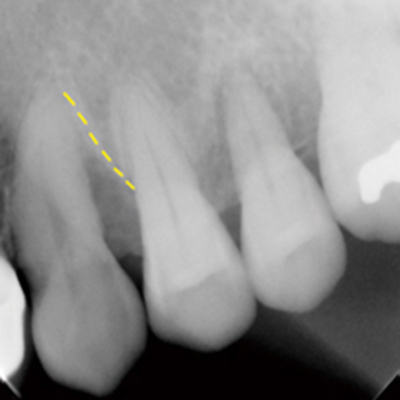

案例1

補骨前

補骨後